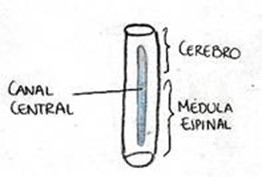

Durante el embarazo, el encéfalo y la médula espinal comienzan a desarrollarse en forma de un plato plano de células que se va a enrollar para formar un cilindro al cual se le denomina “tubo neural”.

El tubo neural es una de las primeras estructuras en el embrión (se le llama así al bebé en sus primeras etapas de desarrollo), del que se origina el sistema nervioso central (SNC).

La parte craneal (porción superior o encefálica) de este tubo, presenta dilataciones y, después de una serie de transformaciones, formará el encéfalo. La parte caudal (porción inferior) mantiene su forma tubular y dará lugar a la médula espinal. El tubo neural forma todo lo que son las estructuras de la columna vertebral, contiene al sistema nervioso central.

Sistema nervioso central. 1-Cerebro 2-Sistema nervioso central (cerebro y médula espinal) 3-Médula espinal